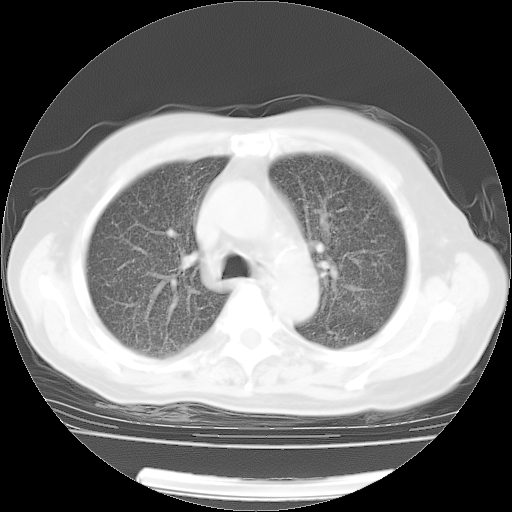

肺部CT平扫未见异常。

4月14日肺部CT